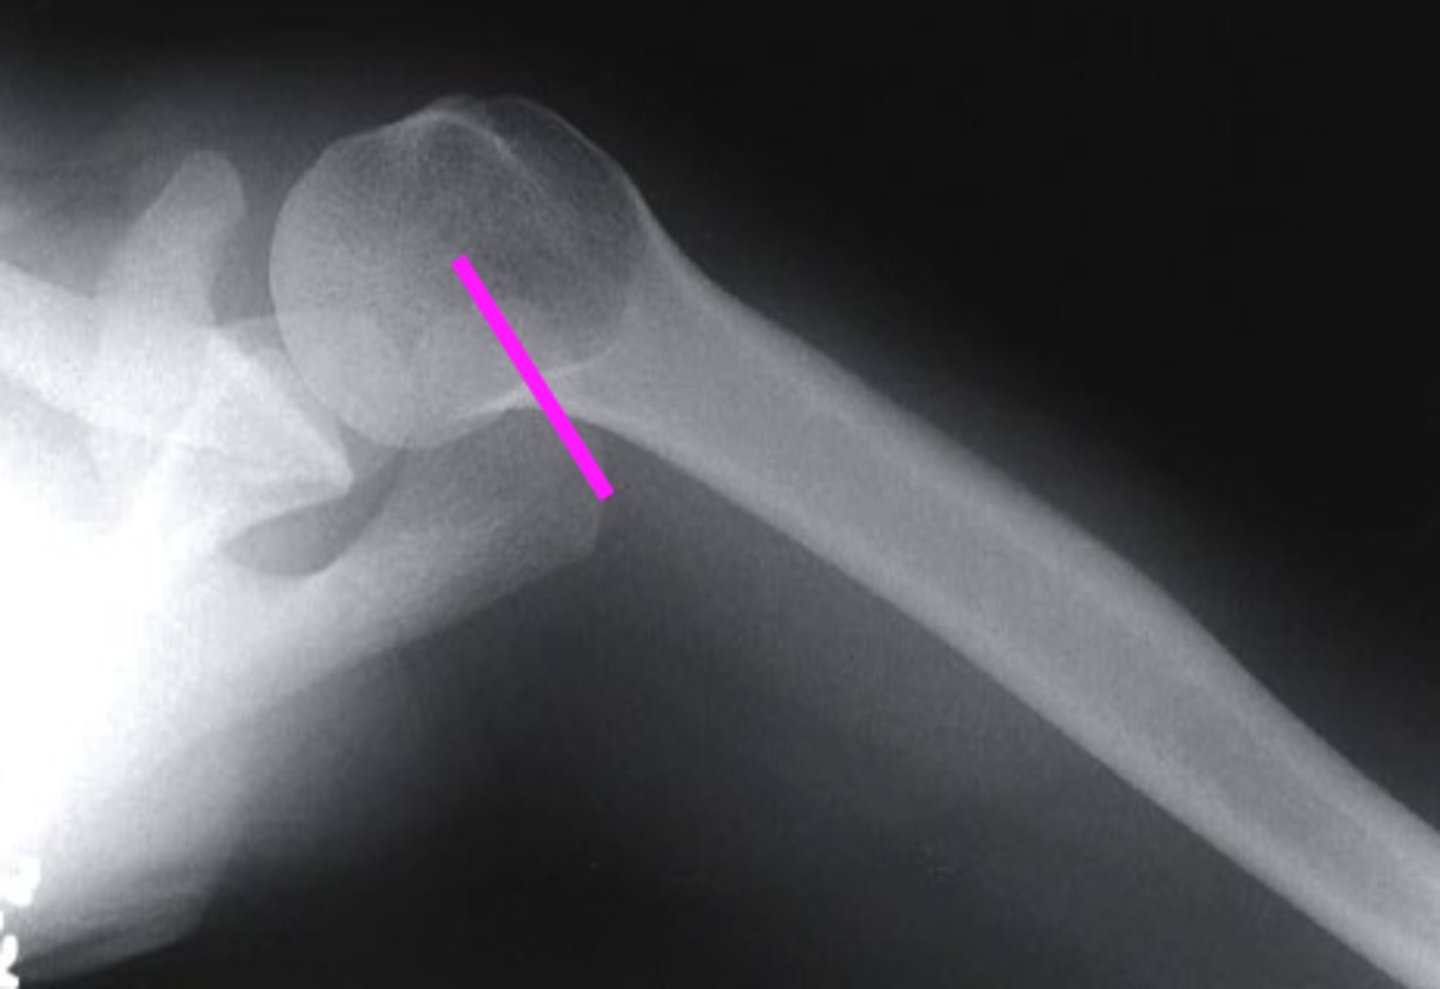

AP + IR

what view is this?

clavicle

what does the pink line point to?

spine of scapula

coracoid process

glenoid fossa of scapula

AC joint

acromion

Humeral Head

lesser tubercle